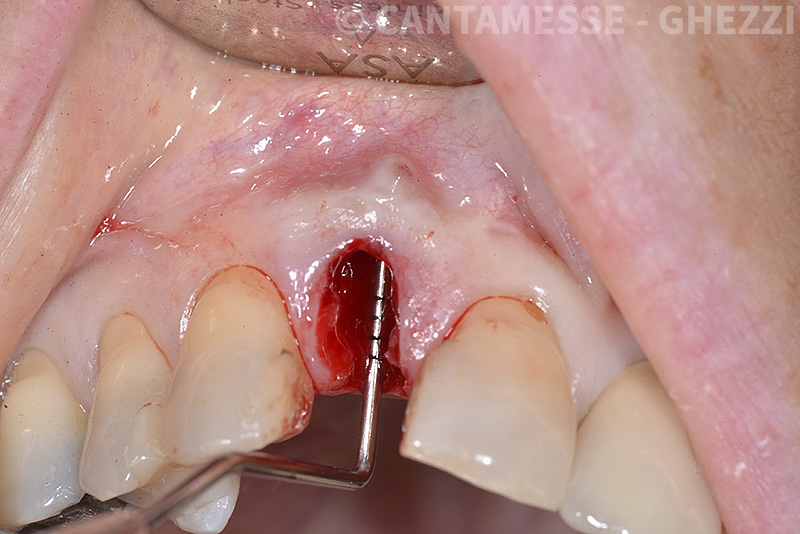

PREMESSA: in seguito all’estrazione dell’incisivo laterale superiore di destra, resasi necessaria per cause batteriche, si decide di affrontare il caso con il posizionamento di un impianto in sostituzione dell’elemento mancante dopo guarigione del sito infetto. Con tecniche rigenerative sia dei tessuti ossei mancanti a causa dell’infezione pregressa, sia dei tessuti gengivali che appaiono inizialmente troppo spostati in alto, si ripristina una corretta morfologia delle parabole (contorni) gengivali e delle papille interdentali (triangoli di gengiva tra due denti vicini).